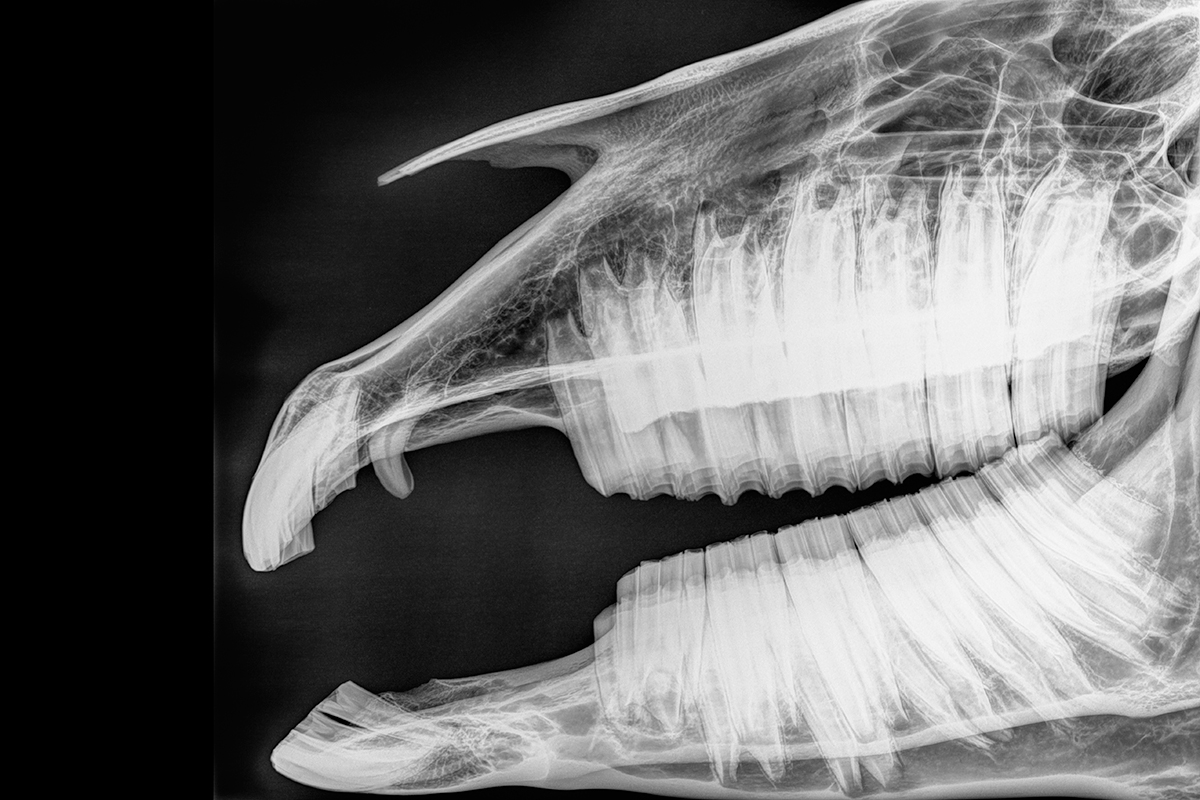

A horse’s tooth root is located at the bottom of the alveolar bone (the bone where the tooth forms) and comes up through the middle of the tooth, stopping before the gum line, according to Wickliffe. Above that is the pulp cavity, a chamber-like area covered by multiple layers of dentin, cementum and enamel.

Horses have hypsodont teeth, found in grazing animals that eat fibrous material. These have high crowns with extra material for all of the wear and tear they experience.

“Most horse’s teeth actually end in cementum around the outside,” Wickliffe says, highlighting an important difference from human teeth. Cementum is softer than enamel and prevents the teeth from shattering under the pressure used to grind food.

Molars are made up of multiple layers of dentin, cementum and enamel. Wickliffe also notes that a horse’s molars and premolars have multiple roots, with most molars having four to five.

Horse incisors, however, have one central root and single layers of cementum, dentin and enamel, similar to human teeth.

◆ X-rays (if needed)

When looking for cavities, dentists will assess what they can see and touch with instruments, and then will use X-rays to see hidden areas, like the inside of a tooth.

“Any exam is going to be broken up between clinical and radiographic findings,” says Hanley.